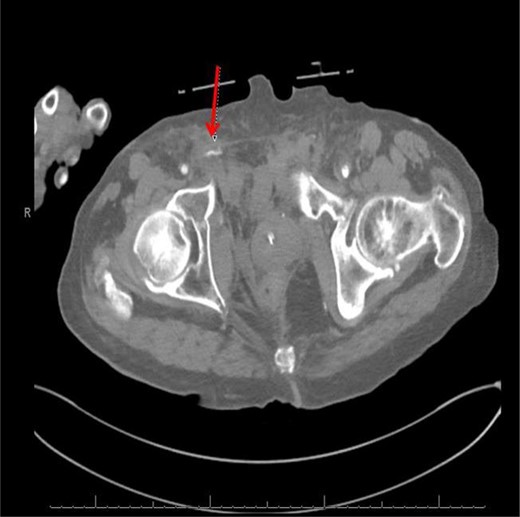

An 84-year-old male was brought by EMS to the emergency room due to a crush injury while pinned under a vehicle for nearly 30 min. The patient was conscious with a Glascow Coma Scale (GCS) of 15, breathing spontaneously, with moderate hypothermia (T = 33.4) and hemodynamically unstable (blood pressure = 108/87, heart rate = 88, oxygen saturation = 100). Patient complained of pain and loss of sensation in his right upper extremity and pain throughout the right lower abdomen, back, right hip and right leg. On physical examination, diffuse tenderness was present at the right hip and pelvis and bruising was present on the right groin and bilateral thighs. Patient had an unstable pelvis on physical exam. The clinical picture of hemodynamic instability, hypothermia and pelvic findings indicated a pelvic fracture and pelvic x-ray demonstrated an open book fracture of the pelvis with multiple fractures throughout the pelvic ring (Fig. 1). Pelvic binder was applied. Patient was transported to computed tomography (CT) yet only CT of the head could be performed before the patient became hypotensive. Patient received packed red blood cells (PRBCs) and fresh frozen plasma (FFP) in the trauma bay which responded to blood product resuscitation. Remaining CT scans were completed which revealed chronic subdural hematoma.

Computed tomography (CT) (axial view) of the abdomen and pelvis demonstrating blush of contrast from distal branch of the right internal iliac artery.

CT abdomen/pelvis with contrast was performed and a blush of contrast was noted posterior to the right pubic bone. Prior to taking patient for exploratory surgery, he was transferred to the interventional radiology suite where a pelvic angiogram was performed revealing an abnormal blush localized to the distal branches of the right iliolumbar artery (Fig. 2). Delayed phase of the angiogram demonstrated early venous filling consistent with a traumatic arteriovenous fistula which was embolized with 300–500 µ of embospheres and three 3 × 2 microcoils (Figs 3 and 4).